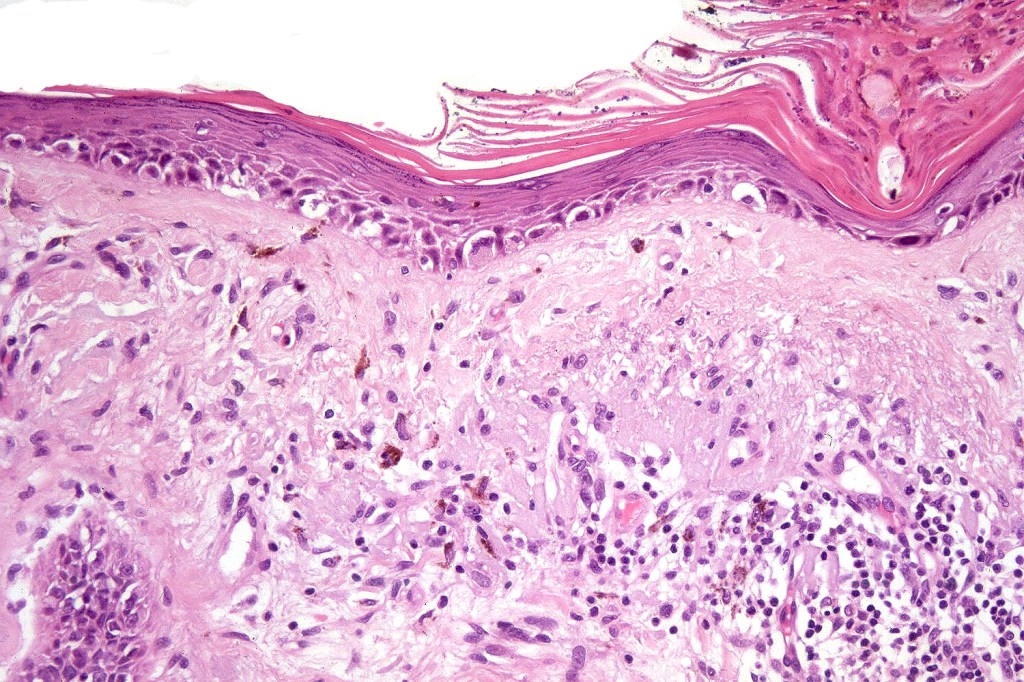

•Epidermal atrophy & solar elastosis

•Atypical melanocytes located predominantly along the basal layer of the epidermis, singly, in short arrays or extensively involving the whole epidermis

•Nest formation present in more advanced cases

•Dermal melanophages & lymphocytic infiltration

Melanocytic (atypical) hyperplasia of sun damaged skin is the most important differential diagnosis. This can be extremely challenging, particularly when examining the margins for completeness of excision. The problem is even worse with MOH’s surgery specimens. Points of distinction include predominace of single cells, abscence of linear arrays of atypical melanocytes, absence of mitoses, nests and Pagetoid spread.